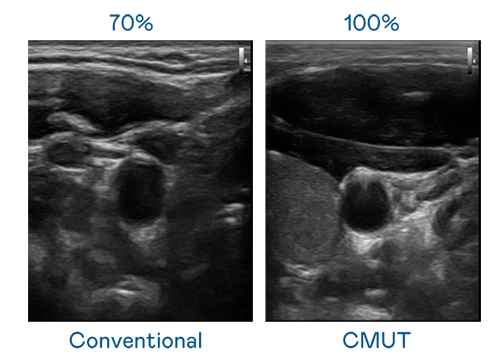

CMUT 技术是一种用电容式微机电元件来产生超音波讯号的技术。与传统 PZT 压电式技术相比,CMUT 频宽增加 30%,更宽频的超音波讯号让影像解析度大幅提升,是实现高影像品质医疗超音波扫描、促进精准医疗发展的关键技术。

大频宽带来超清晰影像

超音波影像的解析度高低,首先取决于探头能发出的讯号频宽。91nba高清免费观看 CMUT 可提供高清晰的超音波讯号,提供高频宽、高灵敏度、影像纹理细节更高的超音波影像,协助医护人员缩短影像判读时间及利用精准的医疗影像进行诊断。